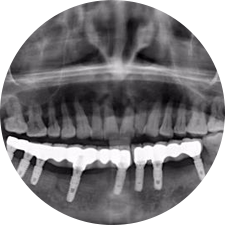

口腔種植是將人工牙根通過手術(shù)植入牙骨內(nèi),獲得牙槽骨牢固的支持,通過特殊的裝置和方式連接牙修復(fù)體,獲得與天然牙功能、結(jié)構(gòu)以及美觀相似的效果。

河北惟德口腔醫(yī)院擁有國內(nèi)豐富的半口/全口、即刻負(fù)重種植案例,十八年案例跟蹤分析,總結(jié)梳理出的各種不同類型的種植案例,Nobel種植體系針對半口/全口缺牙患者,通過4-8顆種植體可快速達到牙齒重建,不僅植入種植體較少,節(jié)省費用,手術(shù)時間更短。

術(shù)前患者CBCT口掃1:1三維重建,模擬手術(shù)過程及預(yù)測術(shù)后治療效果,確定每顆植體植入的適合的種植位點、深度及角度,有效避免損傷頜骨重要解剖結(jié)構(gòu),提高手術(shù)準(zhǔn)確度與安全性。

Noble口腔種植體系基本不受年齡限制,適用于缺牙修復(fù),也適用于牙槽骨萎縮、骨質(zhì)疏松、高血壓、糖尿病、超高齡的患者,即種即用,只需少量微小種植體,便可輕松微痛快速重建全口咬合,特殊力學(xué)設(shè)計,針對許多年紀(jì)較大,骨質(zhì)條件差,身體耐受力差的缺牙老人也能完成“即種即用”,受到廣泛好評。

惟德口腔種植體系是以患者感受為中心,取代傳統(tǒng)種植牙手術(shù)需要翻瓣、打孔、縫合,術(shù)前、術(shù)中、術(shù)后的繁復(fù)流程,采用3D導(dǎo)航微創(chuàng)準(zhǔn)確種植技術(shù),通過數(shù)字化CAD/CAM掃描技術(shù)獲得缺牙患者口腔數(shù)據(jù),以數(shù)據(jù)為基礎(chǔ)重建口腔模型進行模擬種植。